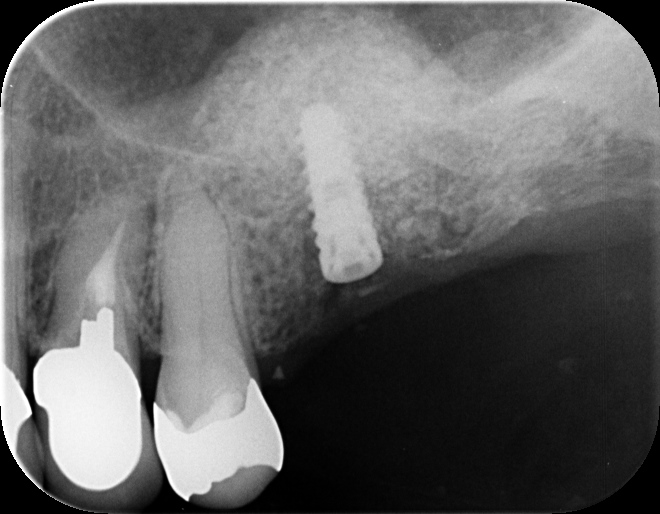

70代女性上あごの骨量の不足を侵襲の少ないラテラル…

患者は70代女性 静脈鎮静下(浅い全身麻酔)にて ラテラルスリット法でサイナスリフト・同時埋入を行いました。 ラテラルスリット法はほとんど腫れない、より確実性のある、患者にやさしいオペ法です。 …